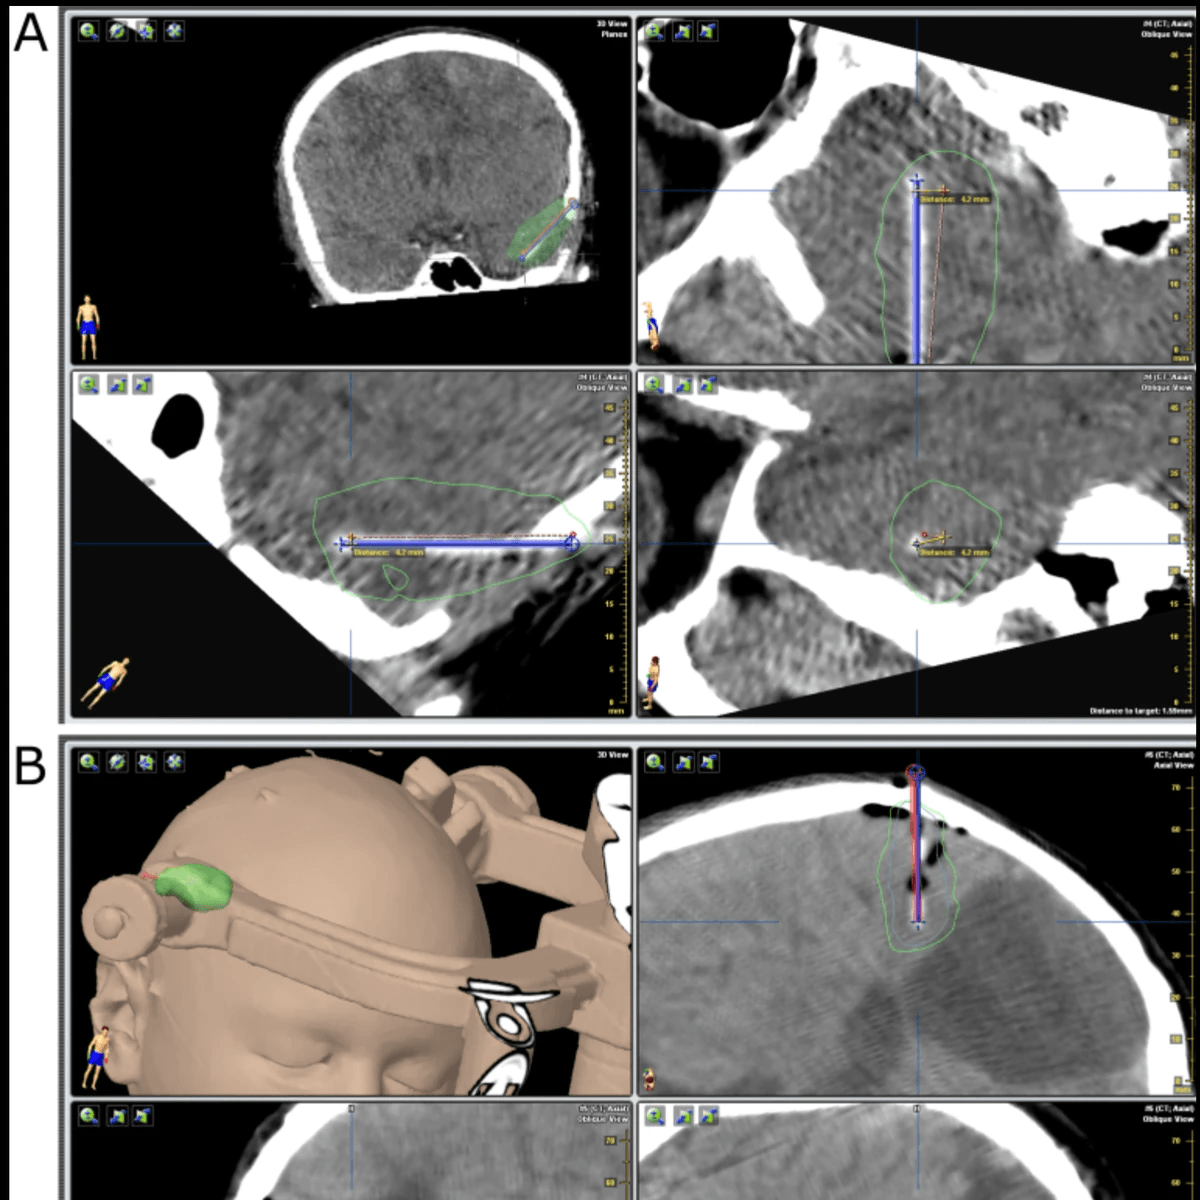

The safety and accuracy of intratumoral catheter placement to infuse viral immunotherapies in children with malignant brain tumors: a multi-institutional study.

Barkley A, Butler E, Park C, Friedman A, Landi D, Ashley DM, Bigner D, Bernstock JD, Friedman GK, Johnston JM*, Thompson EM*. Journal of Neurosurgery: Pediatrics. 2024; 33:359-366. Cover article.